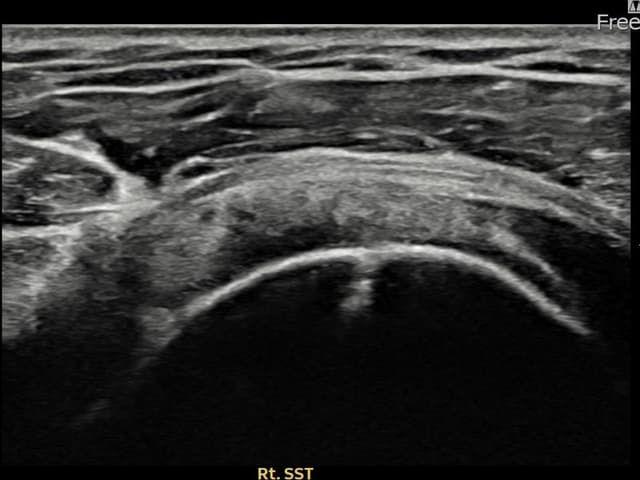

実際の患者様の施術前後の超音波画像。

手術なしで実現できる回復をご確認ください。

[経過期間: 23.09.19~23.11.21]

[縫縮術] 超音波検査にて右 棘上筋腱 関節面側部分断裂(9mm × 4mm (腱厚の約38%欠損))を確認。縫縮術施行後、腱の連続性が回復し、日常生活に復帰されました。